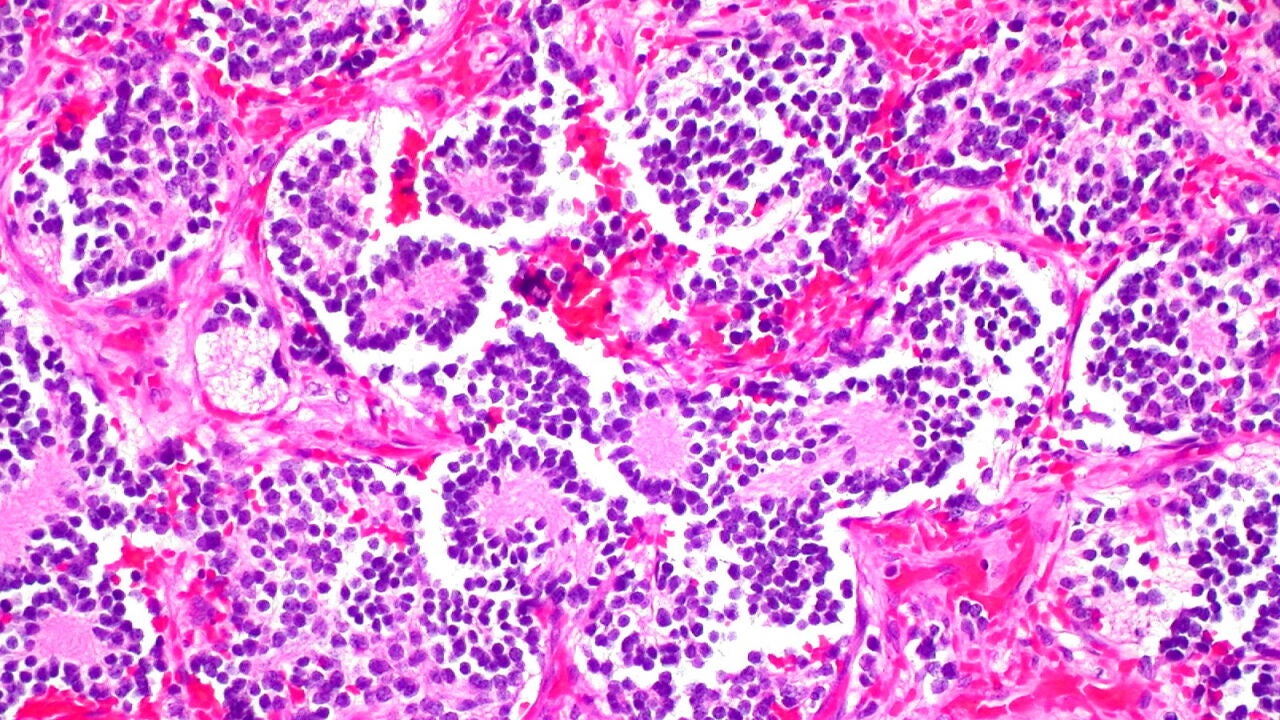

NeuroblastomaEd Uthman

El neuroblastoma es un tipo de cáncer que se inicia en las células llamadas neuroblastos, un tipo de células nerviosas inmaduras que se encuentran en diferentes órganos del cuerpo.